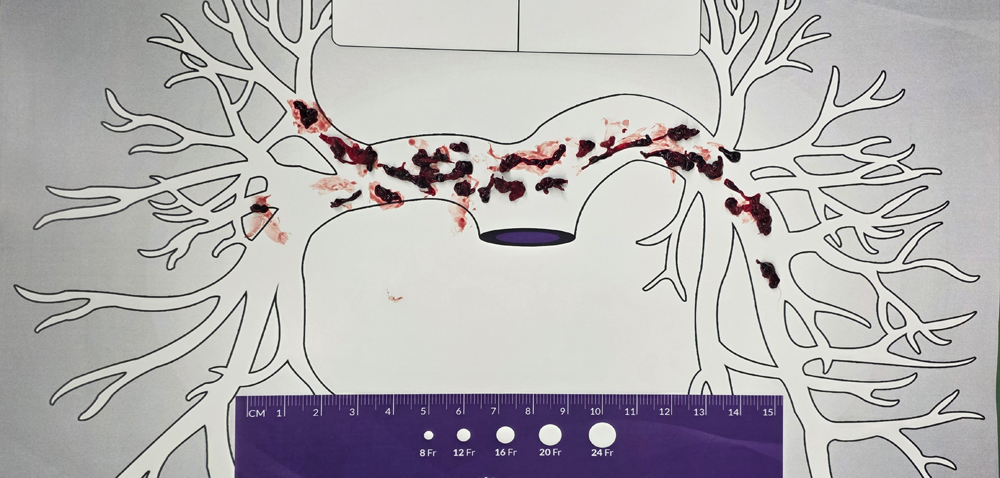

在血管外科赵亮主任的统筹指挥下,手术团队果断决定通过绿色通道行急诊微创手术。术中造影显示,谢先生的双侧肺动脉主干及分支充满了血栓,肺部血流几近中断。张杰主任医师主刀,立即为患者实施了先进的“肺动脉机械血栓抽吸术”,导丝犹如一根精密的“生命吸管”直抵病灶,将堵塞血管的血栓快速、高效地清除。此次手术还创新应用了外周血栓过滤回输装置,该装置也是全国首例在肺栓塞抽吸中单独应用,不仅彻底清除了血栓,更成功回输了近400ml自体血,极大提升了手术安全性。为预防下肢血栓再次脱落引发危险,术者还为患者植入了“下腔静脉滤器”,如同在血栓通往肺动脉的“必经之路”上设置了一张可靠的“安全网”。手术效果立竿见影,术后谢先生的喘憋症状迅速得到缓解。术后第一天即可下床活动,生活基本自理;术后第三天,他已行动自如,恢复如常了。

血栓分布图